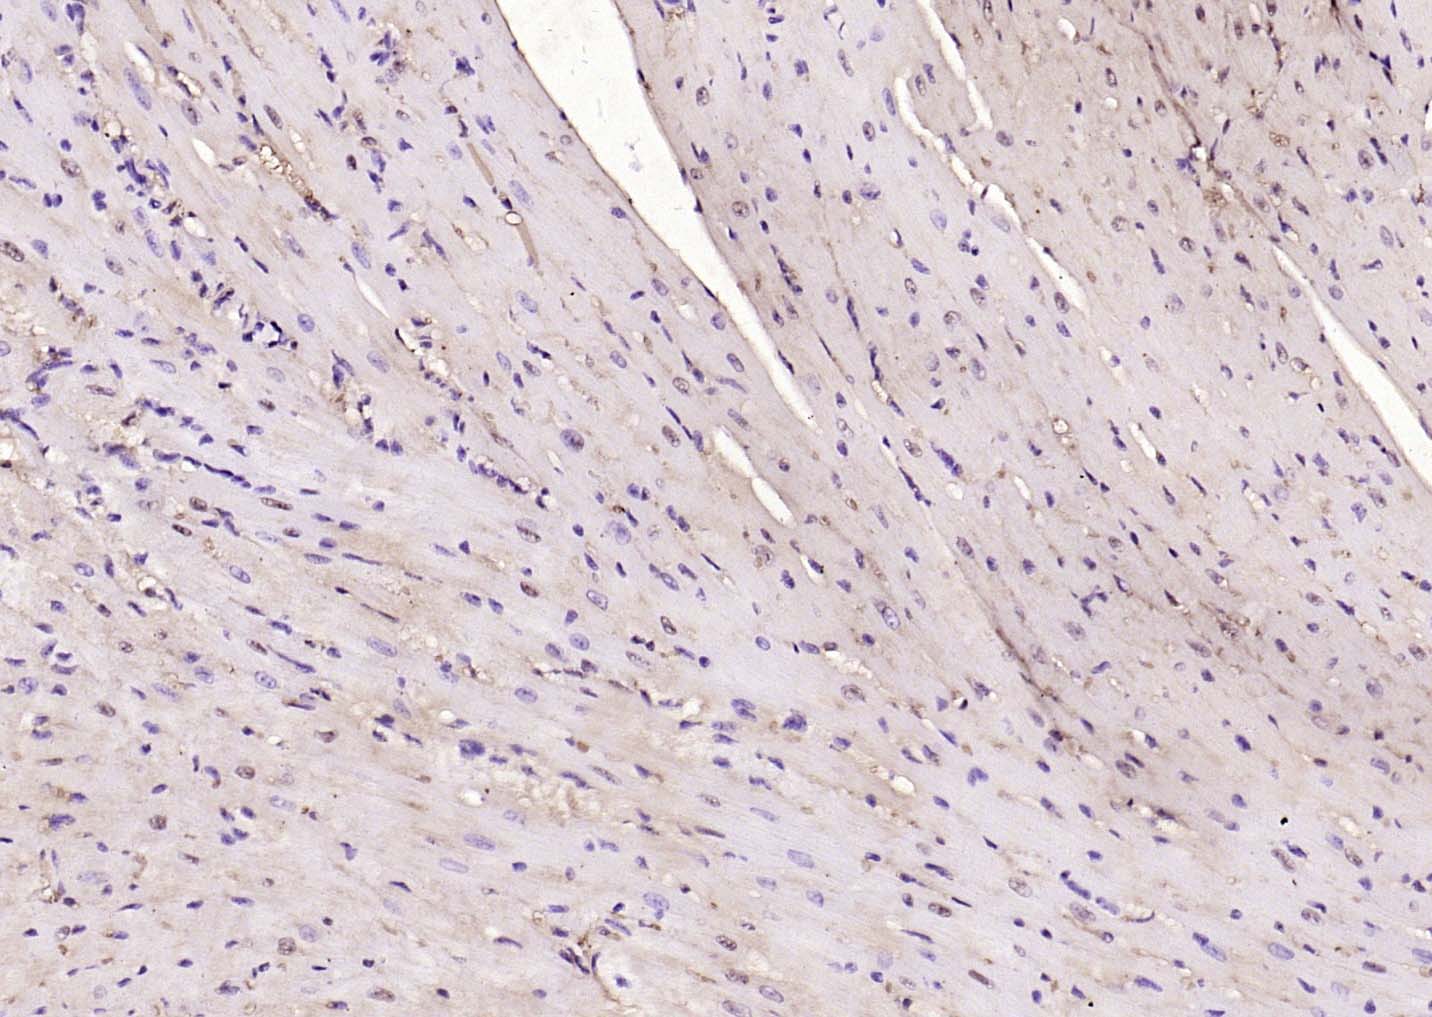

| IHC-P | Human, Mouse, Rat | Cow, Dog, Horse | 1:100-500 |